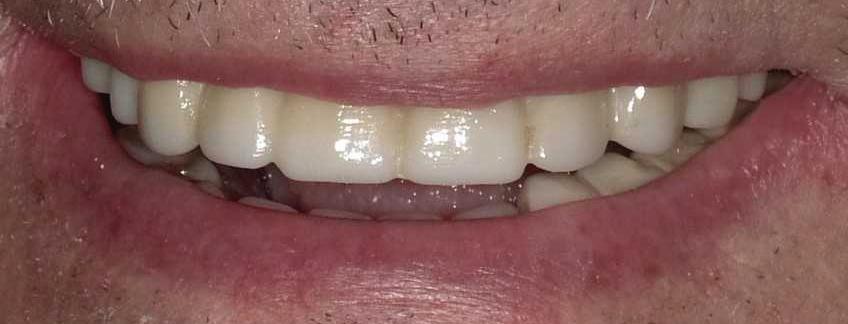

Submitted By Sivakumar Sreenivasan, DMD, MDS Dental Implant Center of Rockville

Can just four implants replace all of the teeth on the top or the bottom of your mouth? Thanks to advances in dental implant technology, that answer is a resounding yes.

Tooth loss is extremely common among adults, especially as we age. Rather than living with the discomfort and hassles of dentures, many people are opting for what is called “all-onfour” dental implant restoration.

An implant is a small titanium

screw that fits inside your jawbone and replaces the root-part of a missing tooth. Minor surgery is required to insert the implants. Once the implant is in place, a crown is attached to give you a highly realistic-looking and functional prosthetic tooth.

You do not need a dental implant for each and every one of your missing teeth. All you need is four precisely placed implants on the top of your mouth, and four on the bottom, to restore your full smile. That’s the beauty of the all-on-four. And because the implant is made of titanium, it has the unique ability to fuse to living bone and function as part of it. So eventually, the dental implant becomes part of the jawbone and serves as a strong, longlasting foundation for your new teeth.

Besides ensuring that your implants are permanently fixed in place, this bone fusion has another important benefit: it prevents future bone loss in the jaw. This helps to maintain a more youthful facial structure – and better

Please see “All-On-Four,” page 62